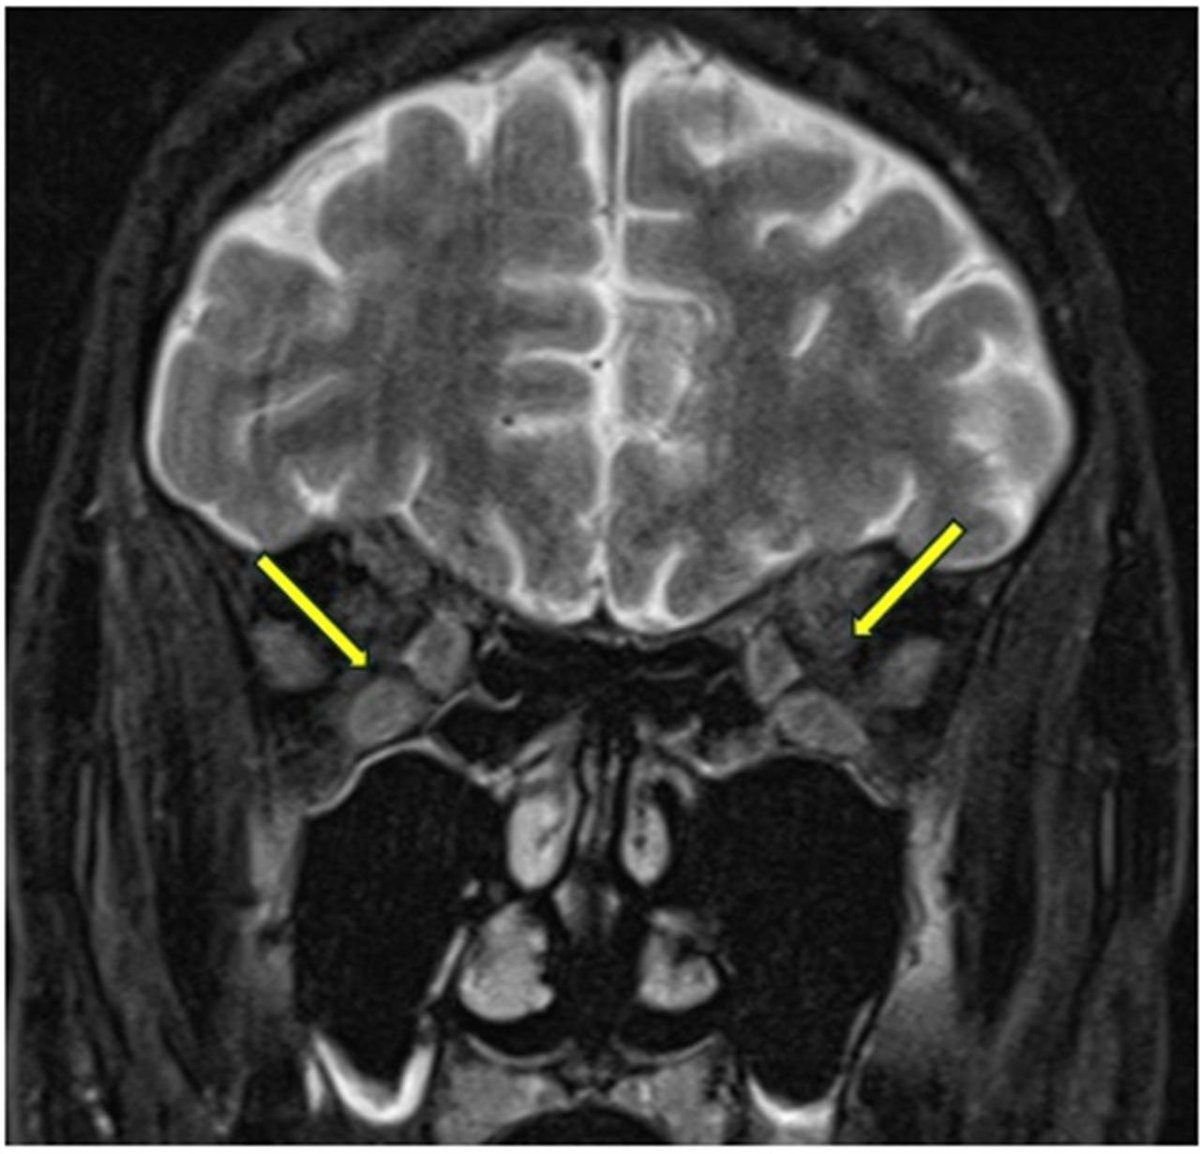

š§ New in Practical Neurology: Paraneoplastic KLHL11 antibody encephalitisĀ presenting with progressive tinnitus, hearing loss, and cerebellar ataxia. KLHL11-IgG - strongly linked to testicular germ cell tumours - shows a distinctive āsparklesāĀ pattern on immunofluorescence š¬